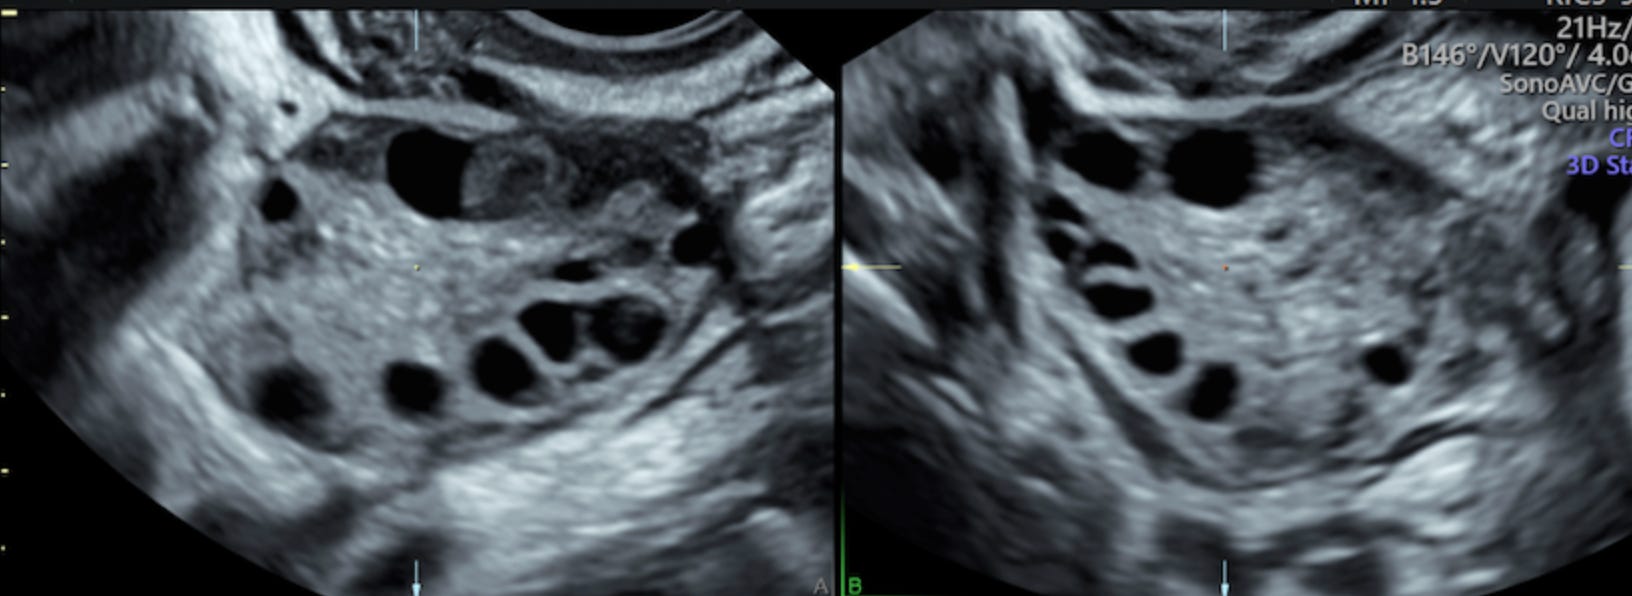

“Oh my god, do you have many eggs!”. “Is that good?” I asked, momentarily forgetting everything I had read about all this. “Yes, yes it is”. She then started to count. Right ovary: 26. Left ovary: 24. There might have been more of them, but at some point I could tell she was bored and gave up counting. I had at least 50 eggs in my ovaries in total. In scientific terms, that was my antral follicle count (AFC). This was good. Phenomenal even — the average for my age is something around 15. I could not quite believe it though, so I asked again: “no abnormality?”. The nurse shook her head. A consultation with the doctor afterwards confirmed what the nurse said.

The so-called “cysts” in my ovary were no cysts at all. They were antral follicles. On the ultrasound above, they are the black holes in the centre of the image. And the opposite of anomalous growths: they are seeds of life. And, like many women with PCOS, I had many of them, although 50 is high even for PCOS. That was good. It felt good.

I exited the clinic and started to cry. Even now, as I write this, I look at the big round black holes that are my follicles with a vague feeling of affection, as if I was looking at the potential of my future children. They are black, gaping little holes to others, maybe even a bit gross; but to me, they are round and beautiful and plentiful — little black holes full of potential. Oh, how annoying will I be as a mom, showing pictures of my newborn!

Of course, these are not actual the monstrous outgrowths the name “cyst” implies, but rather immature follicles, or the structures that contain eggs and the surrounding protective cells. Women with PCOS often have more immature antral follicles3, which leads to the above-mentioned “strings of pearls appearance”. And more follicles is actually what you want during IVF.